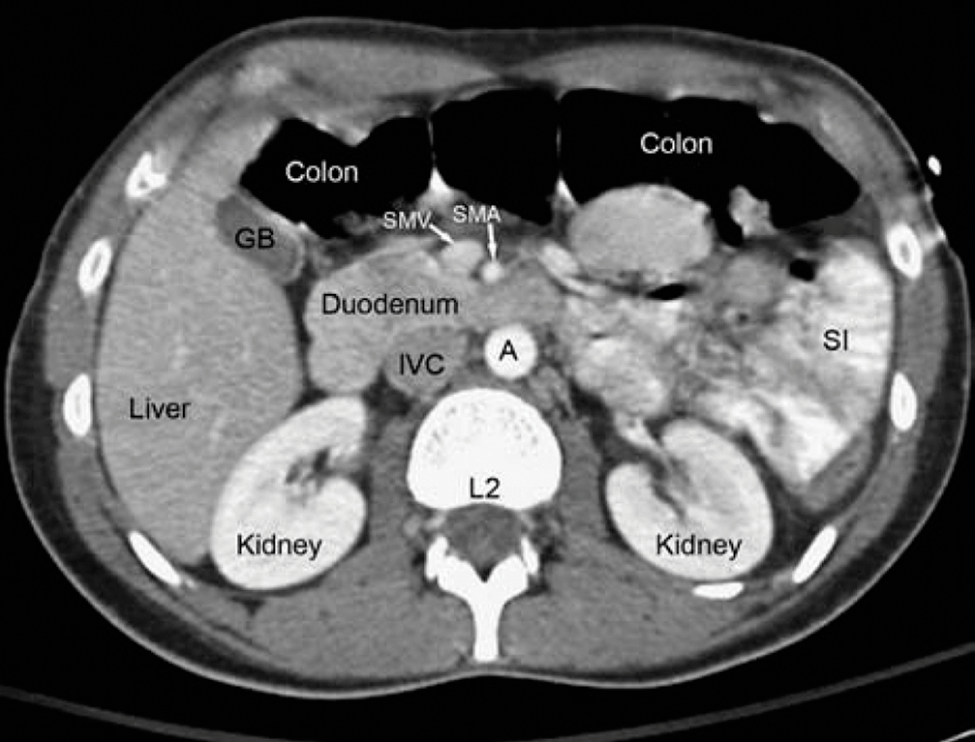

Ct abdominal si pelvis. This technique is able to create pictures of the blood vessels in your belly abdomen or pelvis area. Angiografie ct vase cervicale cu sc inclus 715. Fullscreen computed tomography ct of the abdomen and pelvis is a diagnostic imaging test used to help detect diseases of the small bowel colon and other internal organs and is often used to determine the cause of unexplained pain. Angiografie ct aorta abdomino pelvina cu sc inclusa 1160.

It s performed in a hospital s radiology department or a clinic that specializes in diagnostic. This part of the body is called the pelvic area. We created an anatomical atlas of abdominal and pelvic ct which is an interactive tool for studying the conventional anatomy of the normal structures based on a multidetector computed tomography. Anatomical structures of the abdomen and pelvis are visible as interactive labeled images.

Ct stands for computed tomography. Angiografie ct pelvis cu sc inclusa 715. How an abdominal ct scan is performed a typical abdominal ct scan takes from 10 to 30 minutes. Structures inside and near the pelvis include the bladder prostate and other male reproductive organs female reproductive organs lymph nodes and pelvic bones.